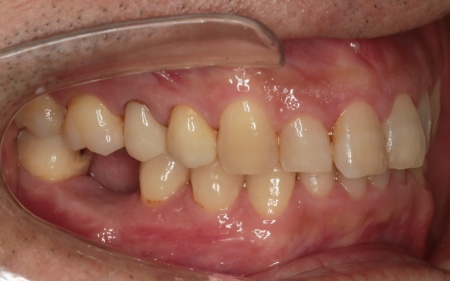

治療中